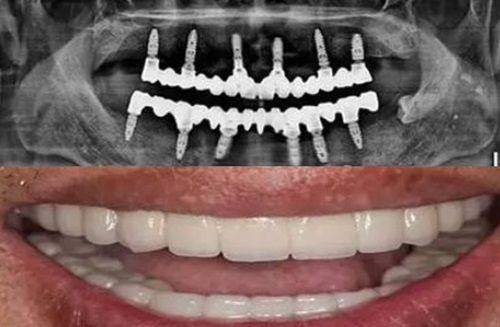

1. 修复原理不同:种植牙是在缺失牙的牙槽骨内植入钛合金人工牙根,等它和骨组织融合后,再连接基台和牙冠,实现接近天然牙的功能与外观。而传统义齿修复中的活动假牙依靠卡环固定在邻牙或黏膜上,固定桥则需磨削邻牙作为支撑。

3. 功能表现差异:种植牙的咀嚼效率能达到天然牙的90%以上,还能防止牙槽骨萎缩。活动假牙咀嚼效率大约只有天然牙的30% - 50%,还可能影响发音和味觉;固定桥虽然稳定性较好,但长期可能因为应力集中导致基牙损伤。